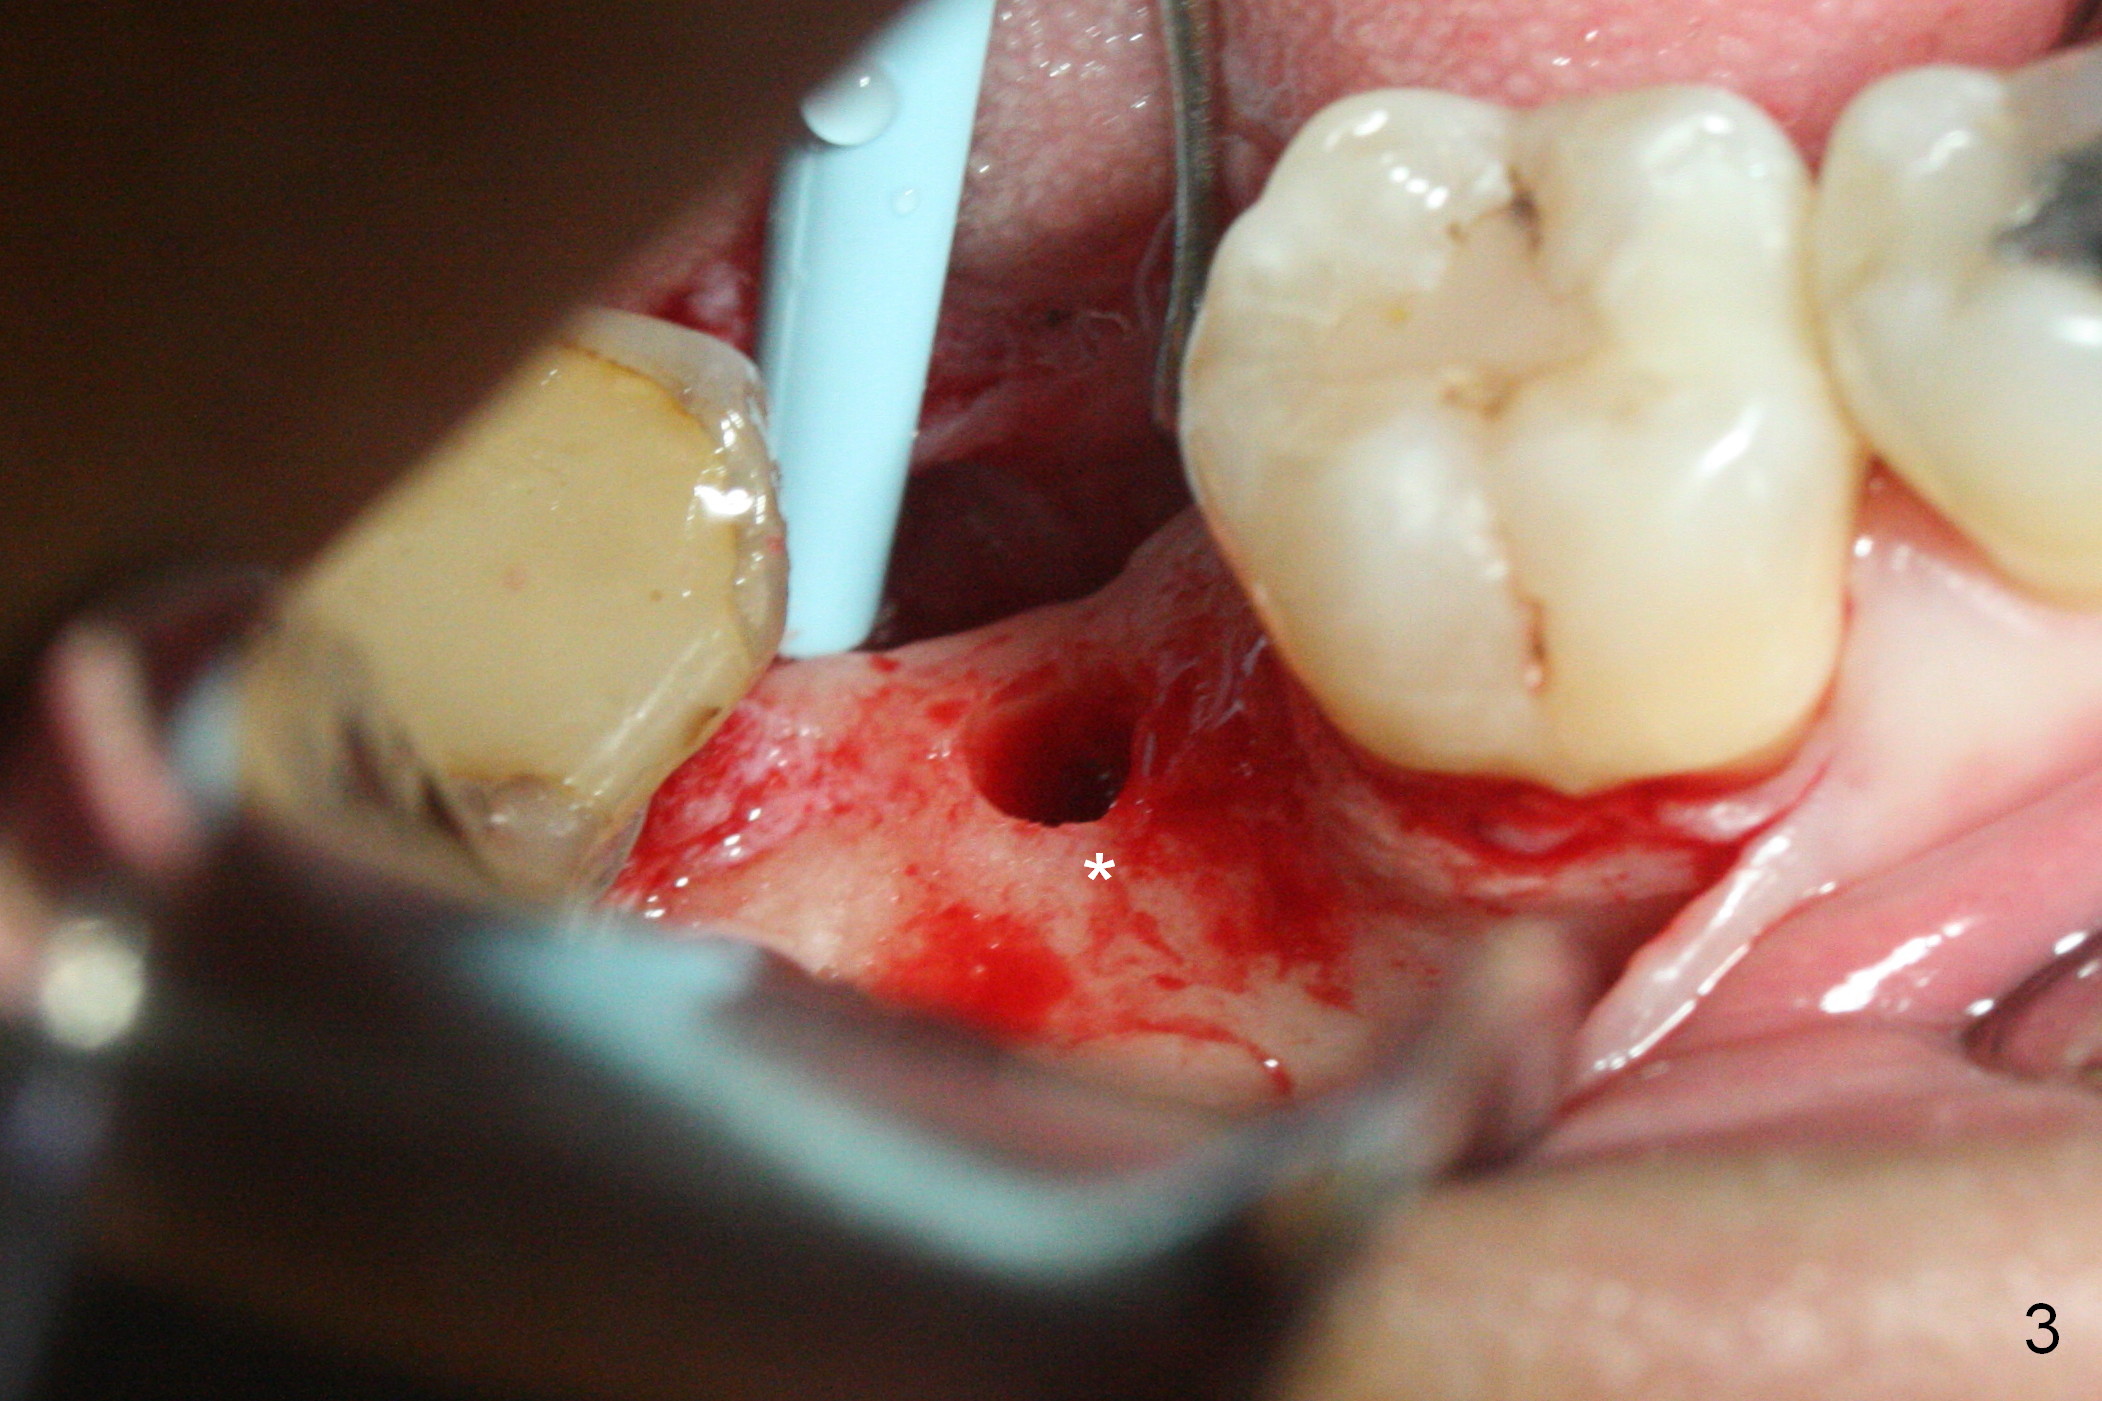

The ridge at #31 is also narrow buccolingually (Fig.1 *). After incision and 1.6 mm pilot drill, a guide pin with 7 mm length is inserted to confirm trajectory and depth; it appears that 11 mm osteotomy has enough clearance from the superior border of the Inferior Alveolar Canal (IAC, Fig.2 red dashed line). Following Marking Bur, 3.3 mm Magic Drill and final drill, the buccal plate seems to be thin (Fig.3 *). When a 4x11 mm IBS implant and 5x4(2) mm pair abutment are placed, the distal thread is exposed (Fig.4 >), the abutment contacts the opposing tooth (data not shown) and there is 2.7 mm clearance from IAC. After increasing the osteotomy 1-2 mm, the implant is placed deeper; the autogenous bone with Osteogen is placed around the plateau of the implant (Fig.5 >), particularly buccally, followed by collagen membrane. When sutures are placed around the abutment, the buccal ridge looks bulkier (Fig.6) than preop (Fig.1). It may remains so long term. The flap surgery makes it possible for simultaneous GBR and reduction in possibility of peri-implantitis. Last, periodontal dressing is applied.